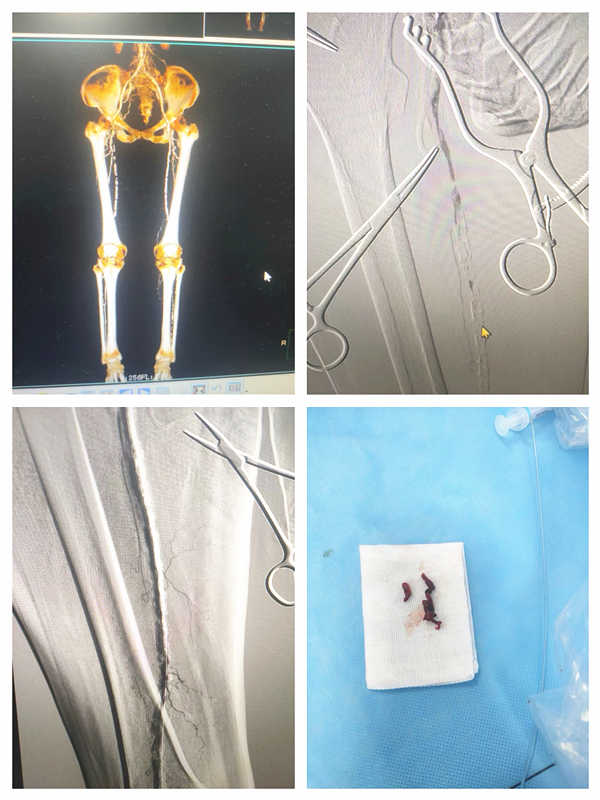

一名九十五岁高龄患者因双下肢间歇性跛行入住胸心血管外科,经CTA检查显示双股浅动脉血管严重钙化、闭塞,胸心血管外科团队成功为高龄患者行下肢动脉溶栓吸栓术,术后造影显示动脉通畅良好。

一名63岁男性因右下肢发凉伴疼痛入住胸心血管外科,经完善检查后明确诊断为下肢动脉硬化闭塞症,胸心血管外科团队为患者行下肢动脉造影,经导管取栓术,取栓导管取出大量陈旧性血栓,复查造影腘动脉、胫腓干、胫前、胫后动脉及腓动脉通畅,患者下肢症状得到改善,立竿见影地解除了患者的病痛。

【医患故事】一位200斤合并心脏瓣膜病、心力衰竭的患者检查时发现腹腔干有一个巨大的“瘤体”----腹主动脉瘤,瘤腔最大直径为:55mm×100mm,瘤体极其扭曲,钙化严重,随时破裂。胸心血管外科黄小龙主任立即组织MDT进行讨论,制定手术方案,科室团队娴熟配合,为患者局麻下实施了腹主动脉瘤腔内隔绝术,成功将覆膜支架放到既定位置,术后造影复查腹腔分支动脉及髂动脉显影良好,血流正常,手术成功!